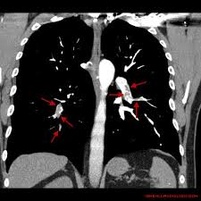

Niestabilność hemodynamiczna u chorych poddawanych embolektomii tętnicy płucnej: doświadczenia własne

Zator tętnicy płucnej jest główną przyczyną chorobowości I śmiertelności wśród chorych poddawanych zabiegom kardiochirurgicznym w trybie pilnym, z całkowitą śmiertelnością wahającą się od 6% do aż 85%. Choć leczeniem pierwszego rzutu jest postępowanie niechirurgiczne lub interwencja przezskórna, to u chorych we wstrząsie kardiogennym leczenie operacyjne ciągle pozostaje metodą z wyboru. Nasz ośrodek regularnie wykonuje operacje embolektomii tętnicy płucnej, których rezultat jest lepszy, niż podają aktualne doniesienia. W związku z tym przeprowadziliśmy retrospektywną analizę wyników leczenia chorych z zatorem tętnicy płucnej i rodzaju anestetyków stosowanych podczas leczenia.

Dokonano przeglądu dokumentacji medycznej 40 chorych. Niestabilność hemodynamiczna występowała w 12,5% przypadków w czasie indukcji znieczulenia i wymagała wytworzenia pilnego zespolenia systemowo-płucnego. Kolejne 17% chorych, którzy byli stabilni podczas indukcji, rozwinęło wtórną niestabilność hemodynamiczną wymagającą pilnego zespolenia systemowo-płucnego podczas otwarcia osierdzia bądź manipulacji w jego zakresie. Jeden chory zmarł podczas hospitalizacji. Chorzy, którzy wymagali wytworzenia pilnego zespolenia systemowo-płucnego podczas indukcji znieczulenia ogólnego, zwykle otrzymywali większą dawkę anestetyków niż chorzy z pozostałych grup. Wśród chorych wymagających pilnego zespolenia systemowo-płucnego podczas manewrów w obrębie osierdzia, u których indukcja znieczulenia przebiegła gładko, nie zidentyfikowano czynników ryzyka niestabilności hemodynamicznej.